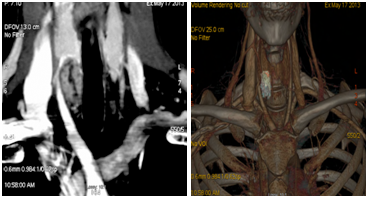

Neck ultrasound (Figure 1A & 1B) revealed a right dominant 2.8cm complex, solid and cystic nodule with intranodular and peripheral vascularity. She was admitted and was treated with intravenous (IV) normal saline. She received 1 dose of IV pamidronate 60mg. Her calcium level improved to 9.8mg/dl and was subsequently discharged. She underwent biopsy of the right thyroid nodule, which was consistent with parathyroid neoplasm possibly adenoma with immunohistochemistry negative for Thyroglobulin, TTF 1, Calcitonin and S 100. She was subsequently referred to endocrine surgery for evaluation of parathyriodectomy. CT scan of neck with 3D imaging reconstruction2 (Figure 2) study confirmed a large well defined nodule with peripheral enhancement suspicious for large right parathyroid adenoma. She underwent minimally invasive parathyriodectomy with fluid aspiration and intra-operative PTH levels fell from 289 pg/ml to 15.8 pg/ml. Pathology (Figure 3) was supportive of the diagnosis of atypical parathyroid adenoma with fragments of hyper cellular parathyroid neoplasm consisting of neoplastic cells with solid nest and trabecular growth patterns with focal capsular distortion and increased mitotic activity. Immunohistochemistry revealed Ki-67 proliferation index 1-3%, bcl-2 positive, diffuse strong and focal weak positive p 53. Post operatively; she was started on calcium and vitamin D supplementation. She is doing well and remains normocalcemic for 2 years following surgical resection with most recent calcium of 9.3mg/dl.

Figure 1A : Ultrasonographic findings consistent with right thyroid nodule with solid and cystic component.1B: prominent peripheral and intranodular vascularity.

Also, in our patient, the parathyroid adenoma was masquerading as a thyroid nodule on ultrasound images. Certain ultrasound characteristics used to distinguish a parathyroid adenoma from thyroid nodule include solid composition, hypo echoic appearance and presence of a feeding polar vessel.18 Ultrasound is inexpensive and noninvasive technique for localization but it needs experienced hands to identify and distinguish parathyroid adenoma from thyroid pathology. Sometimes, US directed biopsy with PTH analysis is required for confirmation.